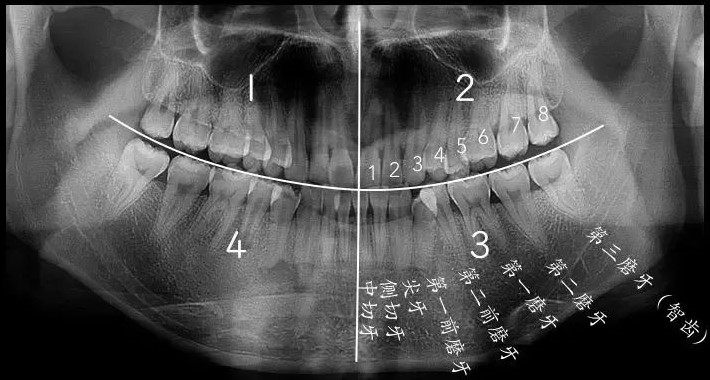

人类有多少颗牙齿?事实上,并非所有人的牙齿数目都一样,一般来说,长出28~32颗牙齿都是正常的,有的人先天缺失牙齿,也有的人先天多牙齿。那什么是智齿?智,也就是聪明,智齿之所以被称为智齿,很大程度上是因为它在成年之后萌出,人们觉得这是心智成熟的标志,于是称之为智齿。

如果我们把正常成年人的口腔分为左上、左下、右上、右下四个区域的话,一般每个区域会有8颗牙齿,长在最后的第8颗牙齿就是传说中的智齿,也是我们的第三磨牙。但是,小编还是要澄清一下,智齿和智商,除了都姓智,没有其他关系。